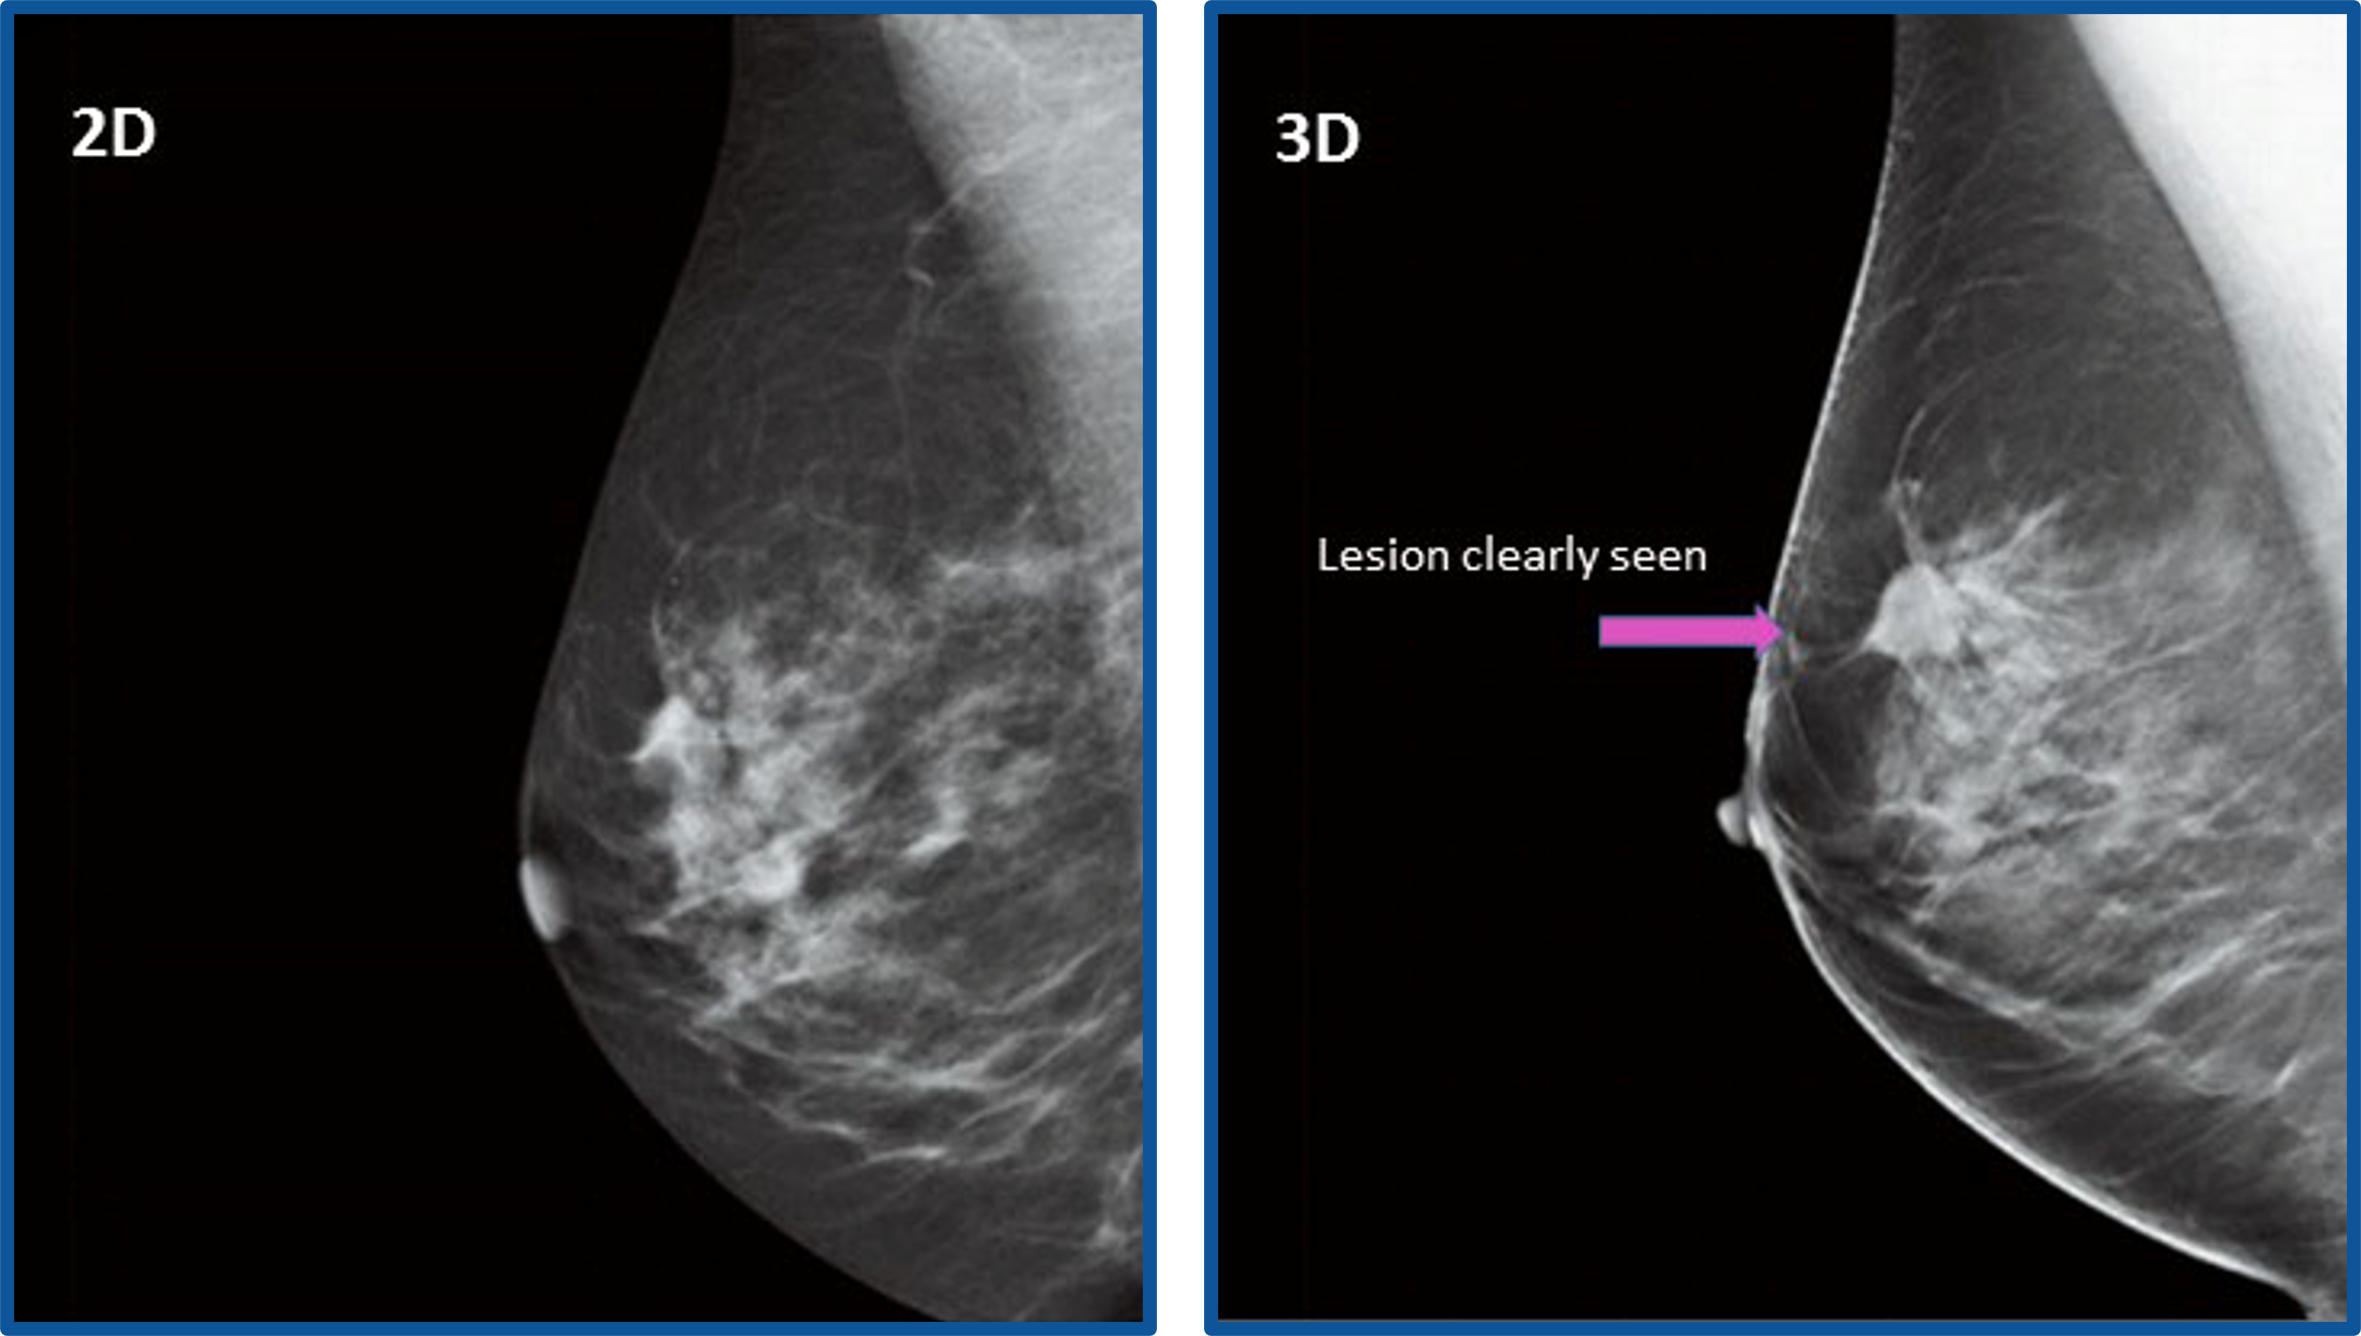

เครื่องเอกซเรย์เต้านมแบบดิจิตอล 3 มิติ (3D Tomosynthesis Mammogram) นวัตกรรมที่ถูกออกแบบให้สามารถถ่ายภาพเอกซเรย์เต้านมได้ทั้ง 2 มิติและ 3 มิติ พร้อมกันได้ในครั้งเดียว และใช้รังสีเอกซเรย์ขนาดกำลังต่ำ ด้วยลักษณะการปรับโฉมของแผ่นกดเต้านมใหม่ทำให้ช่วยลดแรงกดเต้านมได้อย่างดี ทำให้ทำให้ผู้รับบริการรู้สึกสบายยิ่งขึ้น และยังได้ภาพเอกซเรย์ที่มีคุณภาพช่วยให้สามารถตรวจพบความผิดปกติได้มากขึ้น แม่นยำ ตรงจุด ทำให้แพทย์สามารถให้การรักษาหรือเฝ้าติดตามได้ตั้งแต่เริ่มต้น ในขณะที่ยังไม่แสดงอาการ ซึ่งทำให้มีโอกาสในรักษาให้หายขาดได้มากยิ่งขึ้น

แพทย์สามารถดูภาพในแต่ละมิติหรือแต่ละ Slide จากภาพ Reconstruction เพื่อดูขอบเขต และรูปร่างของก้อนเนื้อที่สงสัย สามารถแยกแยะความแตกต่างของไขมันและเนื้อเยื่อ อื่นๆ รวมทั้งท่อและต่อมต่างๆ ในเต้านม เพื่อค้นหาการจับตัวของแคลเซียมที่มีขนาดเล็กมากๆ ที่คาดว่าจะผิดปกติอาจกลายเป็นมะเร็งในอนาคต

- คุณภาพสูง สามารถแยกก้อนเนื้องอกธรรมดาและก้อนเนื้อที่เป็นมะเร็งเต้านมได้อย่างชัดเจน

- เพิ่มโอกาสในการรักษาได้ทันที ตรวจพบมะเร็งเต้านมได้มากขึ้นถึง 65%